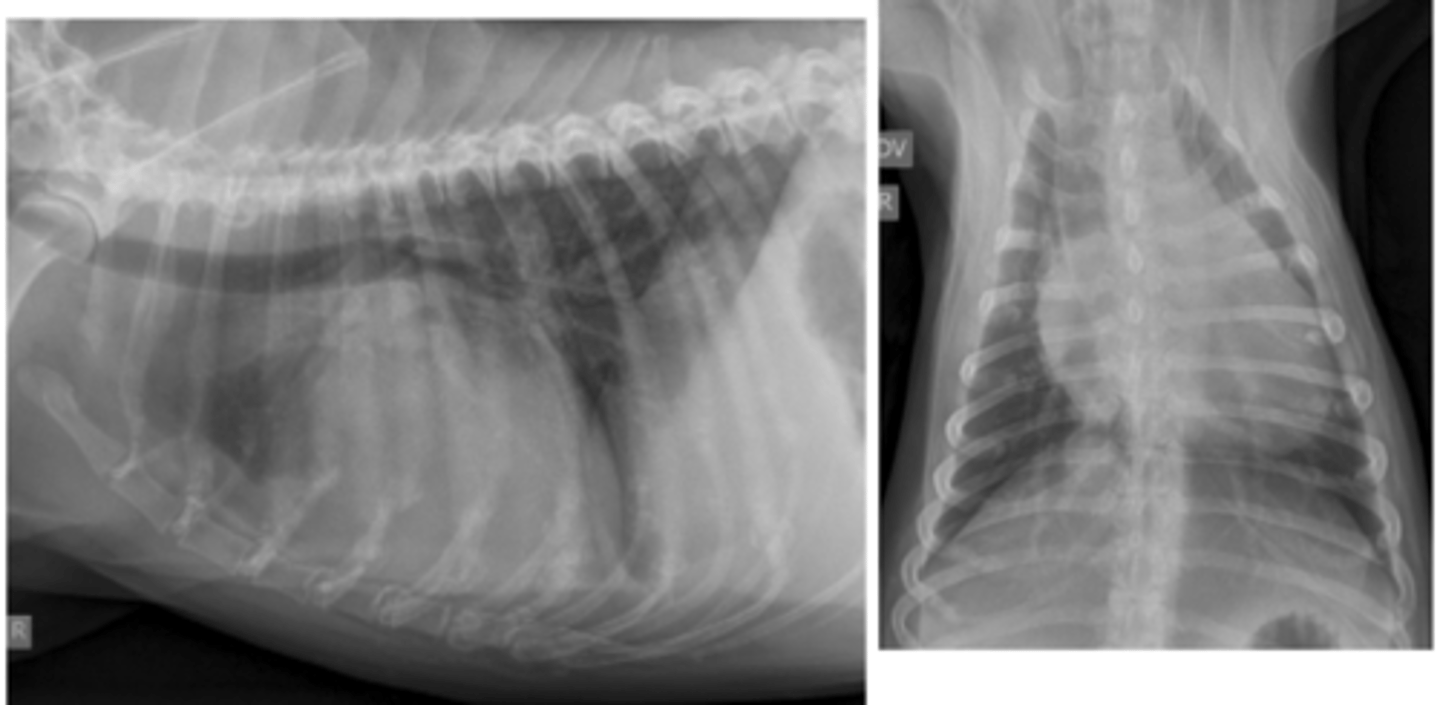

dilatación-torsión gástrica

patología: